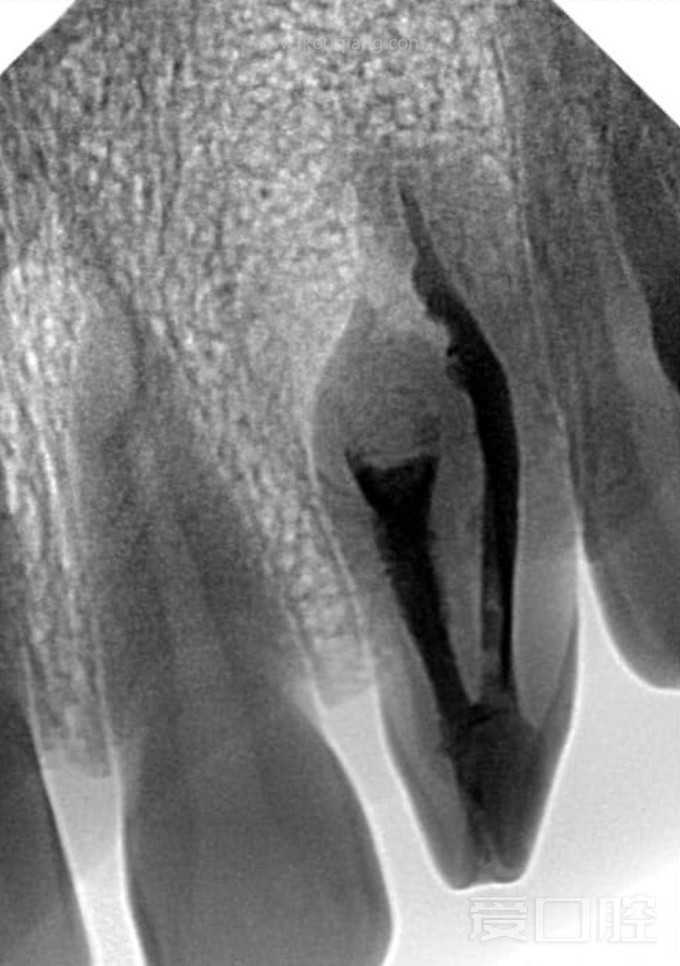

上2牙内陷根充1例

by Zainab Hussien Alzaidy